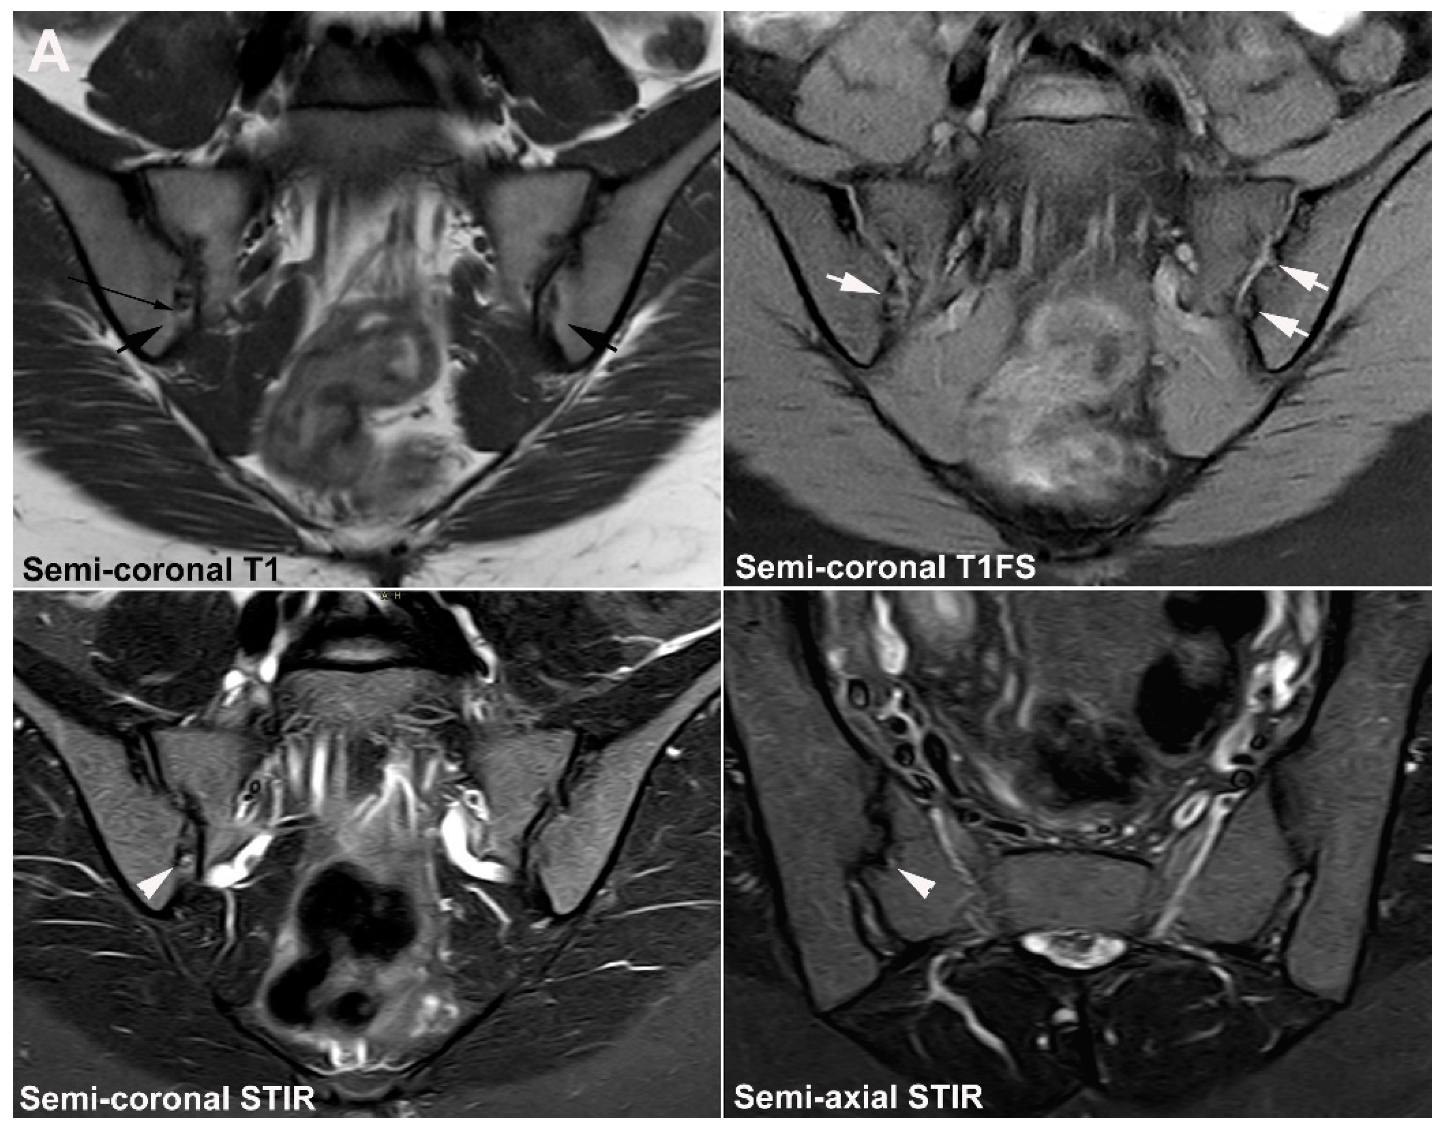

- Weber, U.; Jurik, A.G.; Zejden, A.; Larsen, E.; Jørgensen, S.H.; Rufibach, K.; Schioldan, C.; Schmidt-Olsen, S. MRI of the Sacroiliac Joints in Athletes: Recognition of Non-Specific Bone Marrow Oedema by Semi-Axial Added to Standard Semi-Coronal Scans. Rheumatology 2020, 59, 1381–1390. [Google Scholar] [CrossRef]